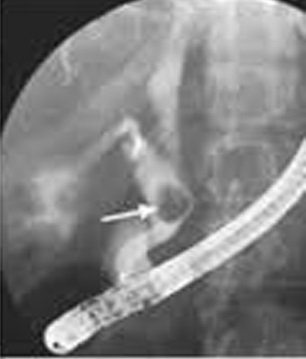

Image ERCP

du syndome de Mirizzi de type IV : Image d'une grand

calcul ( opacite arrondie clair ) encave totalement

dans le canal choledoque ( fleche noir ) . Image du

sonde radio-opaque de ERCP est en vue sur ce cliche

|